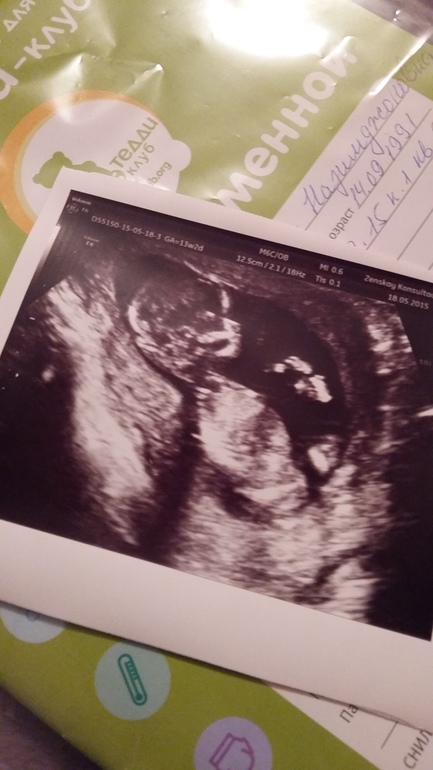

Мы прошли первый скрининг)))

Всё о нашей беременностиНет слов,одни эмоции)))) Спасибо Господи!

Все у нас замечательно)))) А еще забыла, малыш скрестил ножки и нинакакие уговоры не поддался...Врач минут 20 уговаривала...так что, у нас там сюрприз)))

Ну, здорово же, что сюрприз!!! На втором скрининге уже точно разглядите! Легкой и счастливой беременности!

Боже мой, какое замечательное фото! Потрясающе! Поздравляю! Легкой беременности!

Лилечка, как же это Здорово! Поздравляю!!!

Красивый малыш!

Очень четко виден, думаю мальчуган ( личико серьезное, сыночек наверное у тебя будет....)

Лилия

Спасибо огромное))) мы тоже подумали что сынуля, мне постоянно мальчик снится. Он один раз повернулся личиком в монитор и минуты 2 не двигался, и только зевал (так врач сказала),это так прикольно, разбудили мою маську, вот он сонный ничего и не понимал))))

Моя скромняга тоже тут скрытничала, лежала нога на ногу)

Так здорово виден ребеночек..даже присматриваться не надо.))

Малышик скромничает как девочка.))